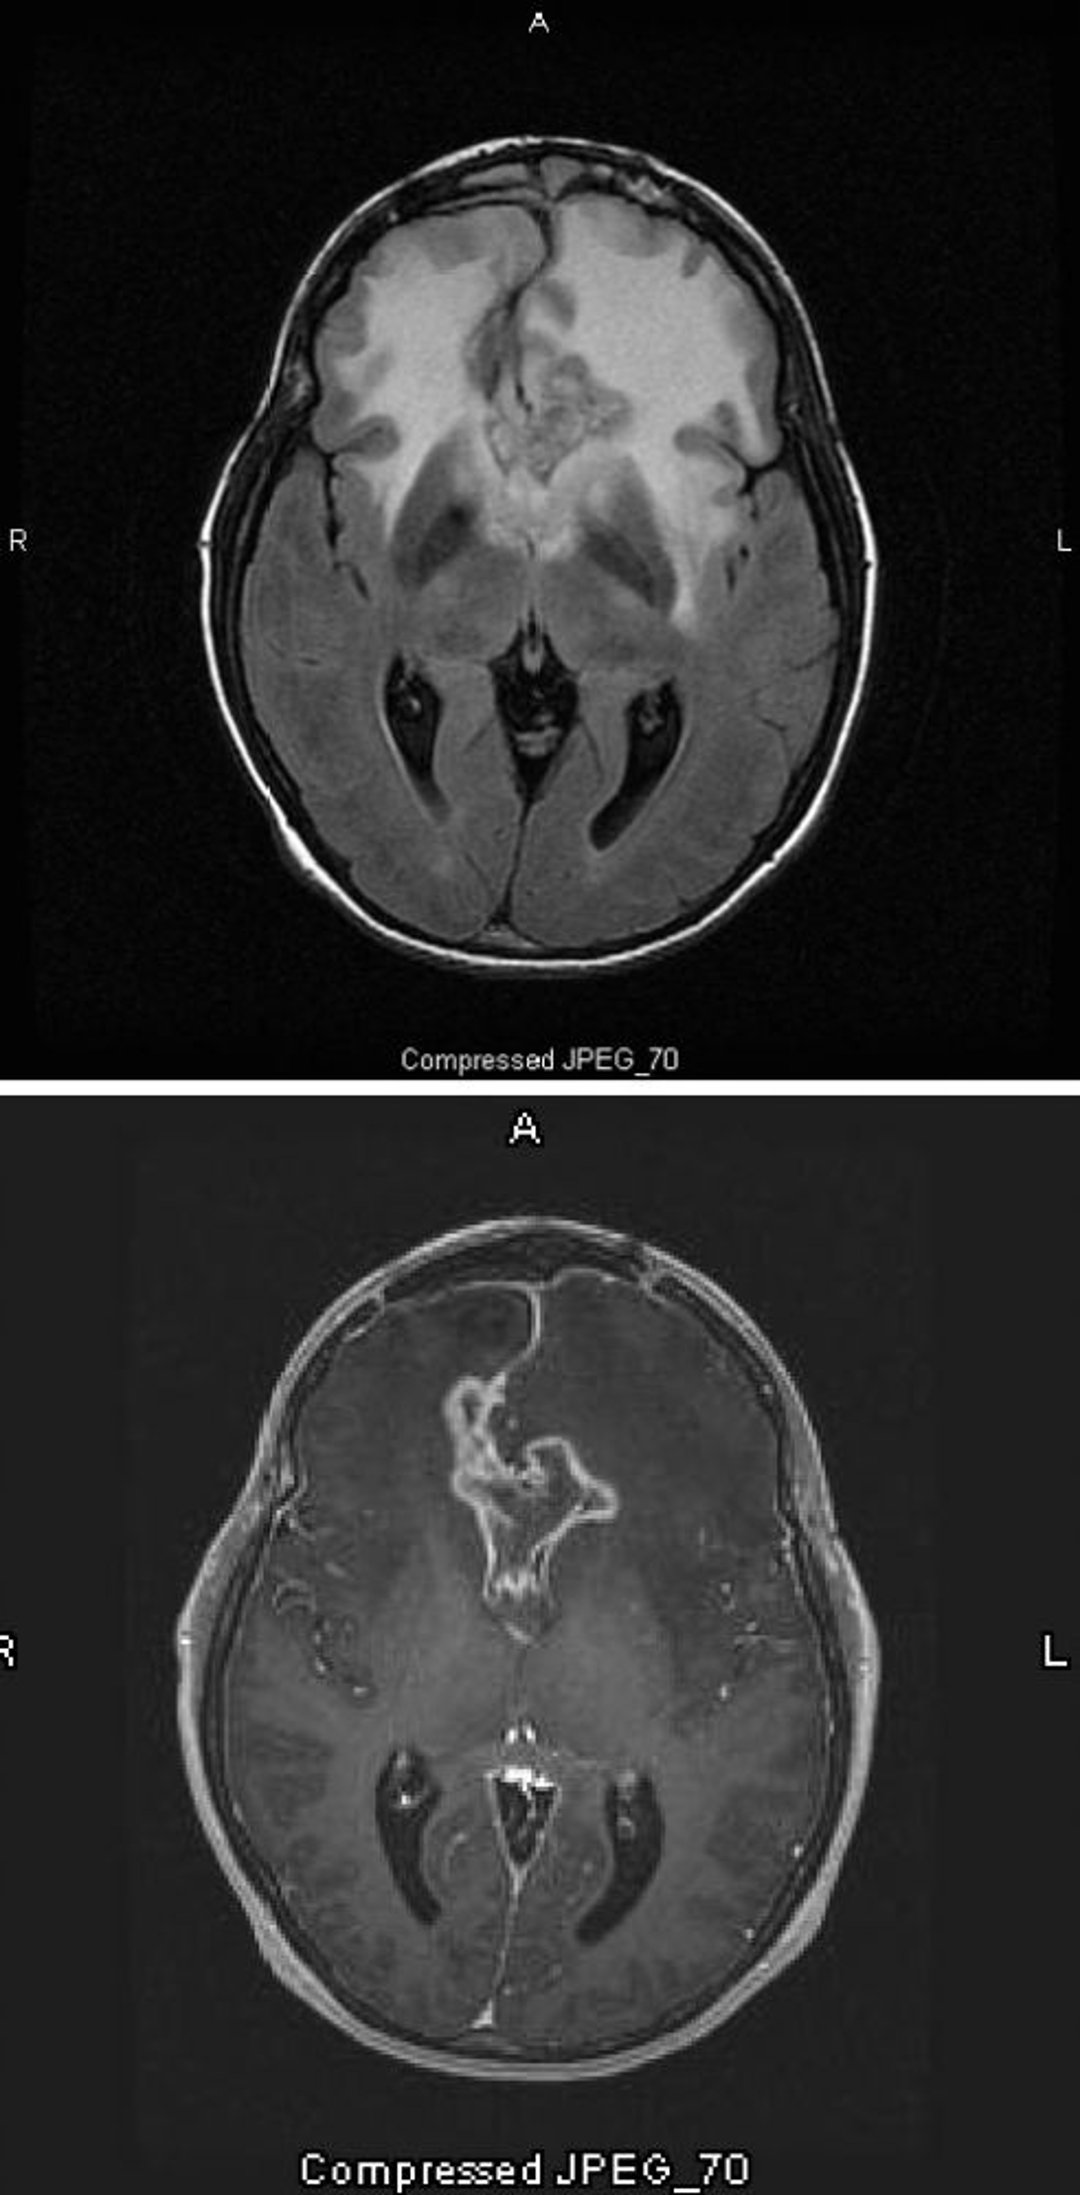

Glioblastoma

Die T2- (FLAIR [fluid-attenuating inversion recovery])-MRT-Aufnahme (oben) zeigt ein großes, bilaterales weißes Signal (Hyperdensität) um ein Glioblastom, das die höchste und bösartigste Form eines Astrozytoms darstellt. Dieses spezielle Glioblastom wird als Schmetterlingsgliom bezeichnet, weil das weiße Signal um den Tumor die Flügel eines Schmetterlings bildet; es wird durch ein Hirnödem verursacht. Auf dem T1-gewichteten Scan (unten) zeichnet der Kontrast den Rand des Tumors nach (Ringverstärkung). Das Ödem erscheint als dunkler Bereich (Hypointensität) auf T1.

Images courtesy of William R. Shapiro, MD.